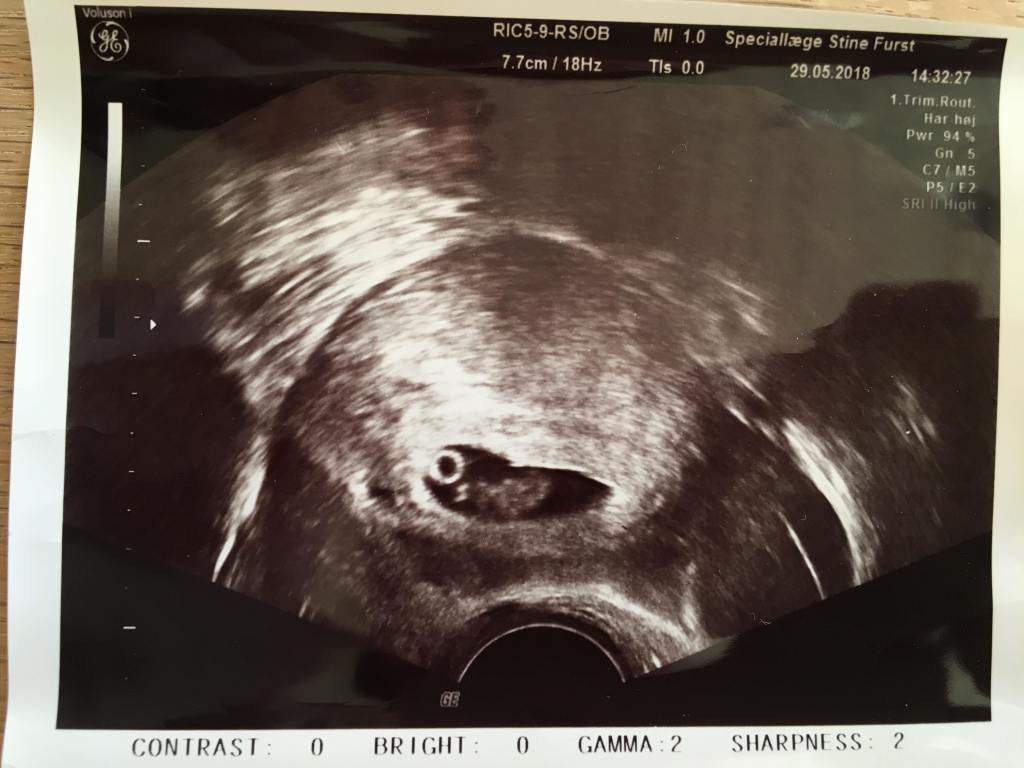

Jeg var meget utålmodig og ville gerne se min lille baby og dens hjerteblink. Martin var derimod mere rolig. Heldigvis fik jeg ham overtalt til at vi fik en såkaldt “tryghedsscanning” i uge 9 på en privat klinik. Jeg kunne simpelthen ikke vente længere. Jeg måtte bare vide at alt var godt. Eller om alt var godt..

Vi kom ind gennem en meget gammel port på Gothersgade. De gamle små mørkebrune trætrin knirkede under os, da vi langsomt gik op mod klinikkens dør. Martin gik forrest og en smilende kvinde tog imod os, da vi kom ind. En anden kvinde styrtede rundt og spurgte på vejen ind i et rum, om det var mig der var Elisabeth. Jeg nikkede og hun sagde “To minutter, så skal jeg være der”. Hun var inde i rummet et stykke tid, kom ud igen, smilede til os, mens hun hastigt hentede en stor vase med blomster, som hun satte ind i rummet. “Nu kan I bare komme ind” sagde hun. Vi trådte ind og der var meget større end jeg havde forventet. I den ene side stod en stor briks. Ved siden af var der placeret en stor indbydende lænestol med en pude i. Blomsterne i vasen stod på et bord op ad de gamle sprossede vinduer, og da kvinden så at jeg kiggede på dem, smilede hun og sagde “Ja, det går jo ikke at her ikke er hyggeligt, når I skal se jeres baby for første gang”. Det føltes som om at de begge kendte os i forvejen og nærmest havde glædet sig til, eller ligefrem ventet på, at vi skulle komme ind på deres klinik.

Selvom det var første gang jeg nogensinde skulle have en ultralydsscanning og se et barn i min mave, føltes det som det mest naturlige i verden. Jeg lagde mig til rette på briksen, trak lidt ned i mine cowboybukser og Martin satte sig i den store lænestol ved siden af og tog min hånd. For enden af briksen var en stor skærm, hvor vi kunne følge med i scanningen. Hun advarede mig om det kolde gele og smurte min mave forsigtigt ind, inden hun satte scanneren på. Og lige dér lå vores lille vidunder. Den lillebitte baby lå på siden med ryggen mod os, så vi kunne se den søde numse og de små ben, som han havde trukket op under sig. (På det tidspunkt vidste vi selvfølgelig intet om at det var en lille dreng der lå derinde og moonede til os).

I 10 minutter holdt vi i hånden og kiggede bare på en kidneybønne, der boblede rundt. En kidneybønne, der dengang var 9+4 uger gammel. Da vi var færdige tørrede hun geléen af min mave med et lille varmt håndklæde. Hun trykkede os begge i hånden og sagde tillykke med vores fine lille baby, før hun forlod rummet og gav os god tid til at samle vores ting.

Da vi kom ud til skranken lå en fin lyselilla mappe klar med dokumenter, der indeholdte al information fra scanningen. Der var målene på vores baby, mit navn og cpr-nummer og nogle andre ting, som jeg ikke helt vidste hvad var. Der var også nogle postkort, men vigtigst af alt, var scanningsbillederne og et link, hvor vi kunne se en video af vores lille baby-Blob boble rundt i min mave. Den video så jeg på flere gange de næste mange uger, hver gang jeg savnede et glimt ind i maven.